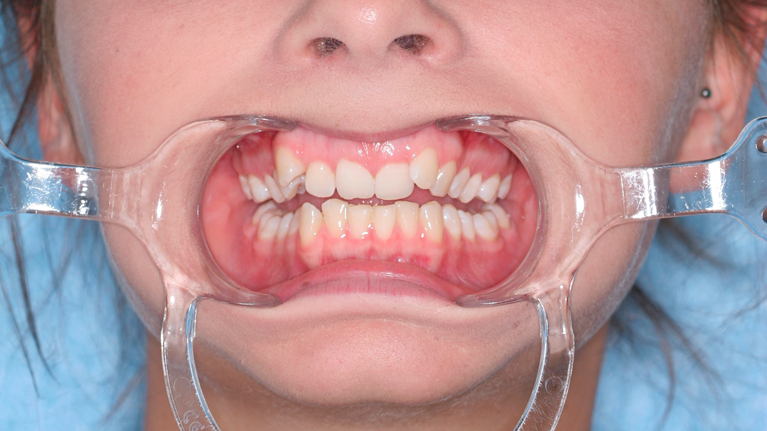

Til konferencen møder du en kirurgisk specialtandlæge fra Kæbekirurgisk Afdeling, muligvis en uddannelsestandlæge og en bøjletandlæge. De fremlægger den foreløbige behandlingsplan, som de forinden har udarbejdet. Du har mulighed for at få uddybet eventuelle spørgsmål til behandlingsplanen.